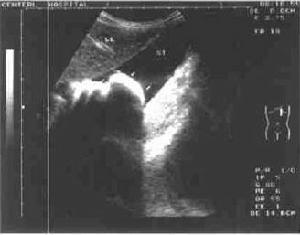

3、B 超檢查:B超對胃石診斷有一定幫助。通常囑患者飲水500~1000ml,坐位或半臥位檢查,可見到胃內有界限清晰的強回聲團塊影像,浮於水上層,並可隨體位變化或胃的蠕動而改變位置。